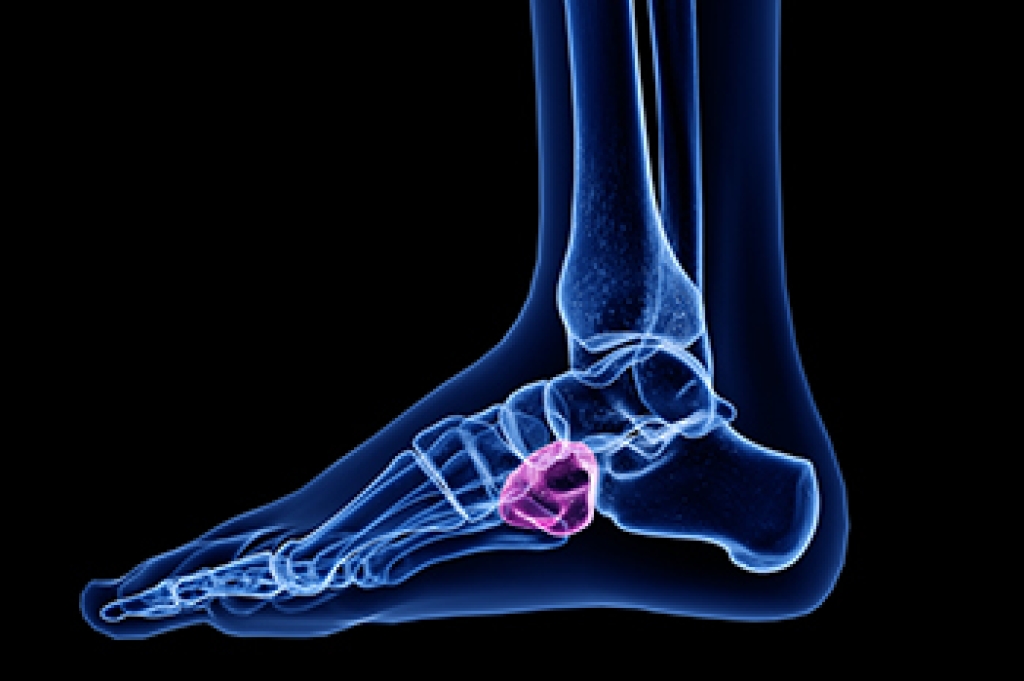

An Achilles tendon rupture is a serious injury involving a complete tear of the tendon that connects the calf muscles to the heel bone. It is common in athletes and active individuals and can abruptly end athletic participation or even a professional career. This injury often results from overuse of the tendon, sudden increases in activity, or long-term degeneration that weakens the tendon over time. Symptoms may include a sudden sharp pain in the back of the leg, a popping sensation, swelling, bruising, weakness, and difficulty walking or pushing off the foot. A podiatrist can evaluate the injury, confirm the diagnosis, and guide appropriate treatment, whether surgical or nonsurgical, to restore strength and function. If you have sudden Achilles pain or loss of function, it is suggested that you seek podiatric care promptly for effective treatment solutions.

The Achilles tendon is a tendon that connects the lower leg muscles and calf to the heel of the foot. It is the strongest tendon in the human body and is essential for making movement possible. Because this tendon is such an integral part of the body, any injuries to it can create immense difficulties and should immediately be presented to a doctor.